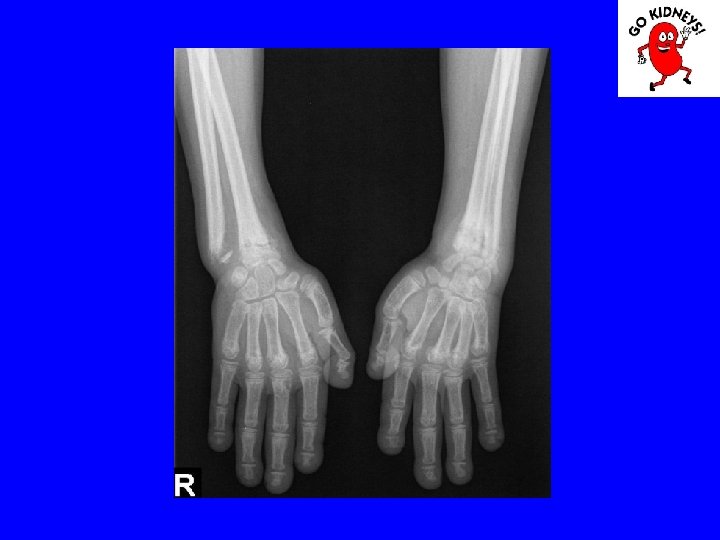

• Diagnosis of renal osteodystrophy 2. radiological changes - subperiosteal resorption of bone is visible in the proximal and middle phalanges, femoral neck and proximal portion of the tibia. The bone resorption is proportional to the aggravation of hyper. PTH. - erosion and disappearance interalveolare jaw septa are signs of severe secondary hyperparathyroidism. - radiological signs of rickets are the lack of bone matrix mineralization in the knees and punches. - osteosclerosis is less obvious in children, in particular in the vertebral body.

Diagnosis • Physical examination may be noted: - delays in growth - presence of signs of rickets or pathological fractures, - high BP. • Laboratory tests show that: - anemia normochromic, normocytic, aregenerativa. - Nitrogen retention and decreased creatinine clearance - metabolic acidosis, hyperkalemia, hyperphosphatemia, - hypocalcemia, hyponatremia - proteinuria or hematuria urinary sediment suggesting glomerular disease old. - low urinary density suggesting a chronic kidney ailment. • Renal ultrasound may show decreased volume of the kidneys • Bone radiography signs of renal osteodystrophy. • Retrograde cystography may help in the diagnosis of reflux nephropathy. • Radioisotope study can give differentiated data for each kidney function.